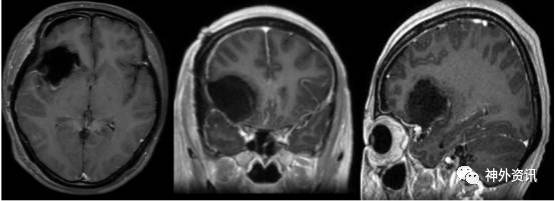

术后影像

术后MR